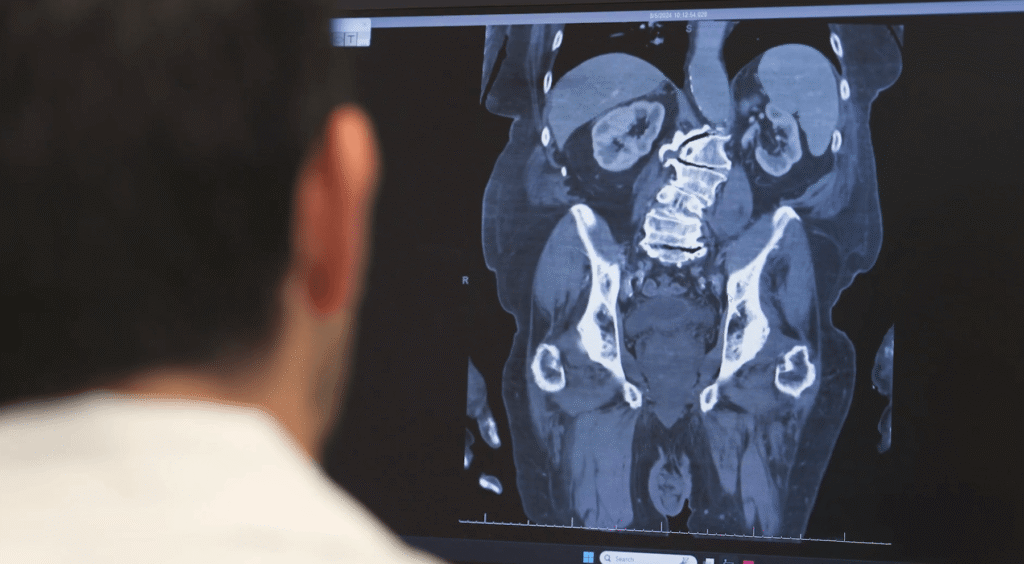

Whether patients are struggling with herniated discs, spinal stenosis, deformity, trauma, or tumors of the spine, Dr. Mazur provides precise diagnosis and personalized treatment strategies using the latest surgical and minimally invasive techniques.

The PNI Spine Clinic in Santa Monica functions as part of a broader comprehensive, multidisciplinary spine health center with PNI spine clinics in Torrance and Burbank. Patients benefit from coordinated care involving specialists in neurosurgery, pain management, physical medicine, radiology, and rehabilitation — ensuring a holistic approach from evaluation through recovery.

Advanced surgical options include motion-preserving procedures, computer-assisted minimally invasive fusion techniques, and leading-edge decompression strategies to minimize tissue disruption and speed recovery.